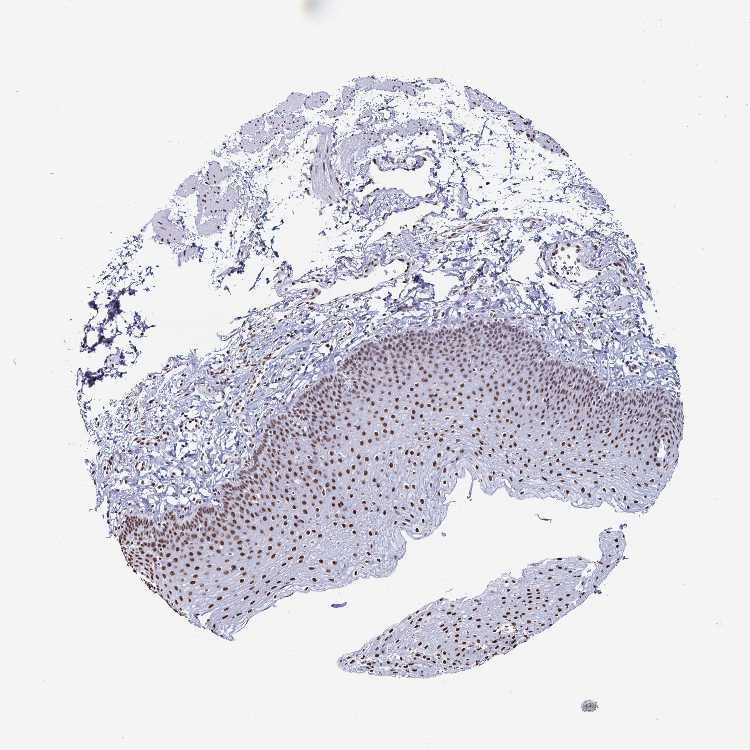

ESOPHAGUS - Antibody stainingi

Antibody staining in the annotated cell types in the current human tissue is reported as not detected, low, medium, or high, based on conventional immunohistochemistry profiling in selected tissues. This score is based on the combination of the staining intensity and fraction of stained cells.

Each image is clickable and will lead to virtual microscopy that enables deeper exploration of all samples and also displays staining intensity scores, fraction scores and subcellular localization as well as patient and tissue information for each sample.

Antibody HPA055334Antibody HPA058450Antibody CAB034012

Squamous epithelial cells MediumHighHigh